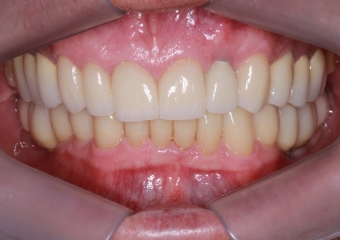

Imagem Próteses Definitivas em Setembro de 2016

Próteses Definitivas e Facetas em Porcelana, em Setembro de 2016

Sorriso Final, em 2016